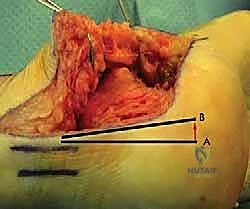

- إزالة النتوءات العظمية الضاغطة (Exostectomy):

يقوم الدكتور هطيف بإزالة الكتلة العظمية الزائدة التي تبرز من الجانب الخارجي للكعب. هذه الخطوة ضرورية جداً لتحرير الأوتار الشظوية (Peroneal Tendons) وتخفيف الضغط عن عظم الشظية، مما يقضي على الألم الجانبي ويسهل ارتداء الأحذية.

- القطع العظمي التصحيحي (Corrective Osteotomy):

إذا كان الكعب قد فقد ارتفاعه أو انحرف بشكل كبير، يقوم الدكتور هطيف بإجراء قطع دقيق في عظم الكعب لإعادة توجيهه إلى محوره الميكانيكي السليم. يتم استخدام طعوم عظمية (Bone Grafts)—تؤخذ غالباً من حوض المريض أو طعوم صناعية—لرفع الكعب المنهار واستعادة زاوية بوهلر الطبيعية.